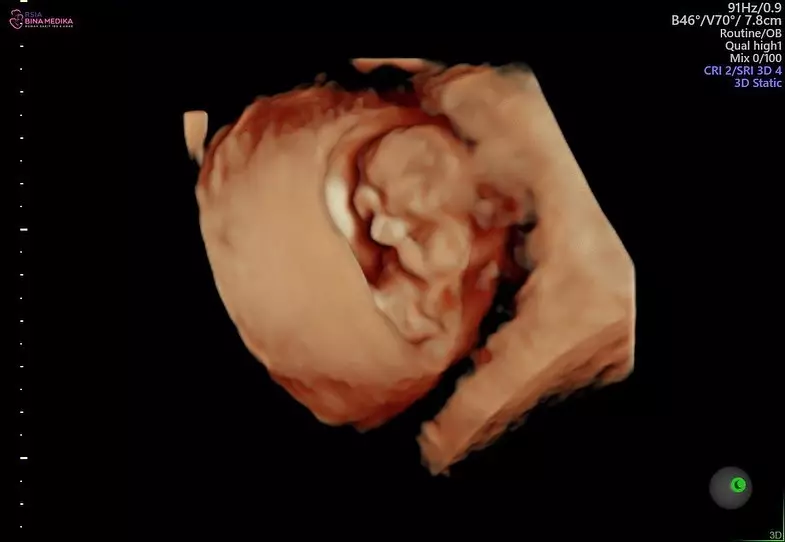

5. Sebagai calon orangtua, pasangan ini pun kembali mengunjungi dokter belum lama ini untuk memantau perkembangan si kecil.

foto: Instagram/@audimarissa

8. Bayi dalam keadaan sehat itu juga disebut sang dokter dalam posisi selayaknya orang berdoa nih.

9. Karena belum memiliki nama, Anthony dan Audi memberikan panggilan "Bao Bao" untuk sang anak lho.

foto: Instagram/@anthonyxie_

10. Dengan perasaan bahagia, Audi menjelaskan "Bao Bao" berarti kesayangan. Ia pun meminta doa dari warganet agar Bao Bao selalu diberikan kesehatan.